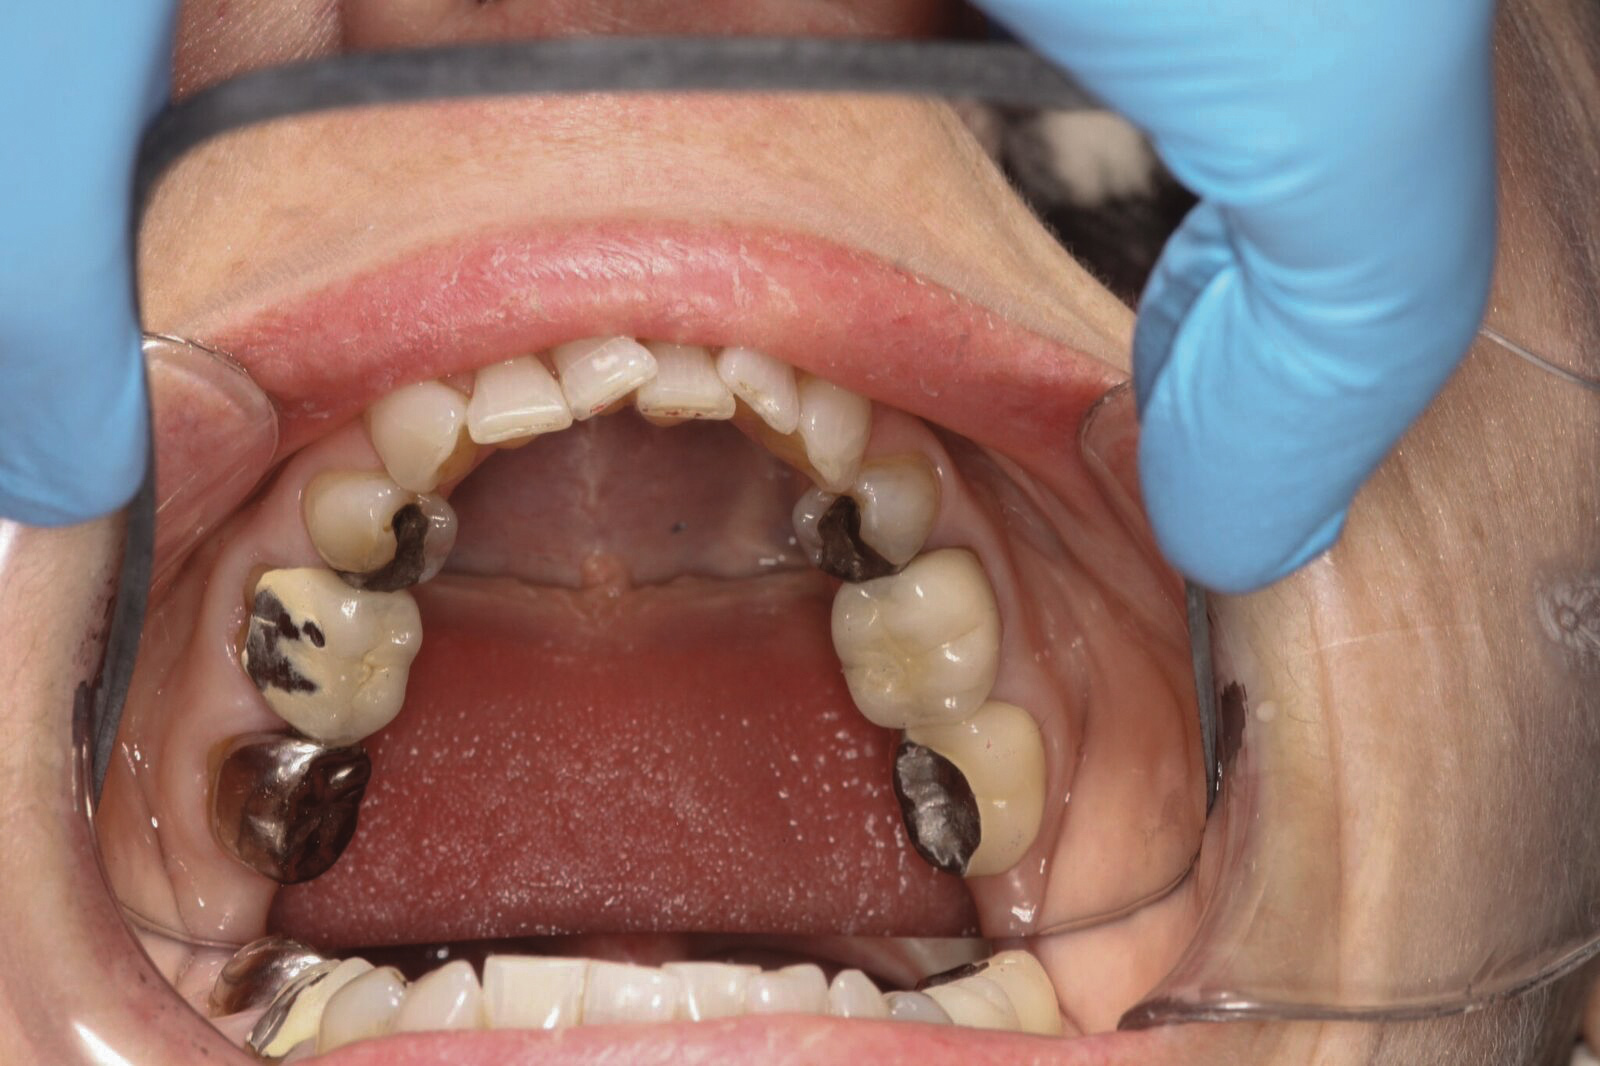

Dental sleep medicine (DSM) is a field in dentistry dedicated to the use and research of oral appliance therapy for the management of snoring and OSA. Oral appliance therapy is a noninvasive alternative to PAP therapy. Oral appliances fabricated by dentists with training in dental sleep medicine are commonly used to reposition the lower jaw forward to increase upper airway patency. Dental professionals have been recognized as being part of the multidisciplinary therapeutic team for the management of OSA because of their prime position of constant examination of the oropharyngeal areas. There are several oropharyngeal features contributing to the development of a narrow upper airway. These features are easily identifiable during a routine dental appointment, such as a large and scalloped tongue (Figure 1), narrow maxilla (Figure 2), small mandible (Figure 3), and retrognathic mandible (Figure 4). Combining clinical history intake, oropharyngeal examination, and the use of validated screening questionnaires, such as the STOP-Bang, dentists can screen for signs and symptoms of OSA and make recommendations for further diagnostic testing.

(3.) Small mandible with lingualized teeth.

Figure 3